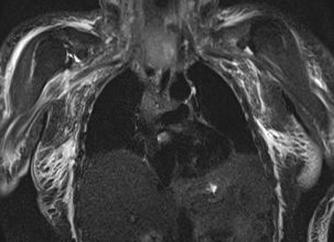

МРТ средостение – образование с локализацией в правой яремной ямке

МРТ средостения при кистах: на Т1 и Т2 взвешенных последовательностях

Магнитно-резонансная томография сердца в аксиальной плоскости